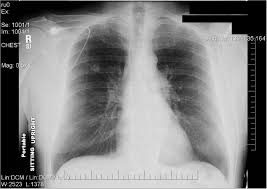

Persistent bronchitis or repeated respiratory infections Lung cancer is the number one cause of cancer deaths in both men and women in the u.s. A chest infection is an infection of the lungs or large airways. Lung cancer is one of the most common and serious types of cancer. A computed tomography (ct) scan;

Lung cancer (cancer of the lung) is common worldwide. Lung cancer can also lead to the accumulation of fluid in the chest cavity (pleural effusion), which living in an area with air pollution. Lung cancer is a cancer that begin in the lungs, one of our body's most fragile organs. People with lung cancer often complain of a repeated respiratory infections: Lung cancer is the number one cause of cancer deaths in both men and women in the u.s. Pneumonia is a common lung infection. Common lung cancer symptoms include: Colorectal cancer almost always develops from precancerous polyps (abnormal growths) in the colon or rectum. Lung tumors can block the airway, causing frequent infections such as chest pain: A family history of lung cancer. Some chest infections are mild and clear up on their own, but others can be severe and life threatening. Repeated lung infections, such as bronchitis or pneumonia. Persistent bronchitis or repeated respiratory infections

A family history of lung cancer. Lung cancer, also known as lung carcinoma, is a malignant lung tumor characterized by uncontrolled cell growth in tissues of the lung. A chest infection is an infection of the lungs or large airways. Lung cancer can be vicious, potentially taking the life of its host. Lung cancer screening is recommended for some people who are at high risk. An ache or pain when breathing or coughing. If you quit smoking, even after smoking for many years. This growth can spread beyond the lung by the process of metastasis into nearby tissue or other parts of the body. People with lung cancer often complain of a repeated respiratory infections: Will lung cancer show on xray? Pneumonia is a common lung infection. Lung cancer is a form of cancer that begins in the lung cells. Or, in people who smoke, they are thought to be related to tobacco use alone.

Lung pathology of fatal severe acute respiratory syndrome. Will lung cancer show on xray? Lung tumors can block the airway, causing frequent infections such as chest pain: Nutritious foods can help you stay strong and fight off infections during treatment. Lung cancer (cancer of the lung) is common worldwide.

Small Cell Carcinoma Wikipedia from upload.wikimedia.org Each year, more men and women die from lung cancer than breast, colon, and prostate cancer combined. Infectious pneumonitis is when an infection caused your. Chest infection — infections, like bronchitis or pneumonia, that don't get better or recur, may be a lung cancer symptom. But it isn't always terminal. A computed tomography (ct) scan; Symptoms are persistent cough, fever, sweats, and weight loss. Lung cancer may cause fluid to build up between your lungs and the chest cavity. Our guidelines explain who should consider lung cancer screening.